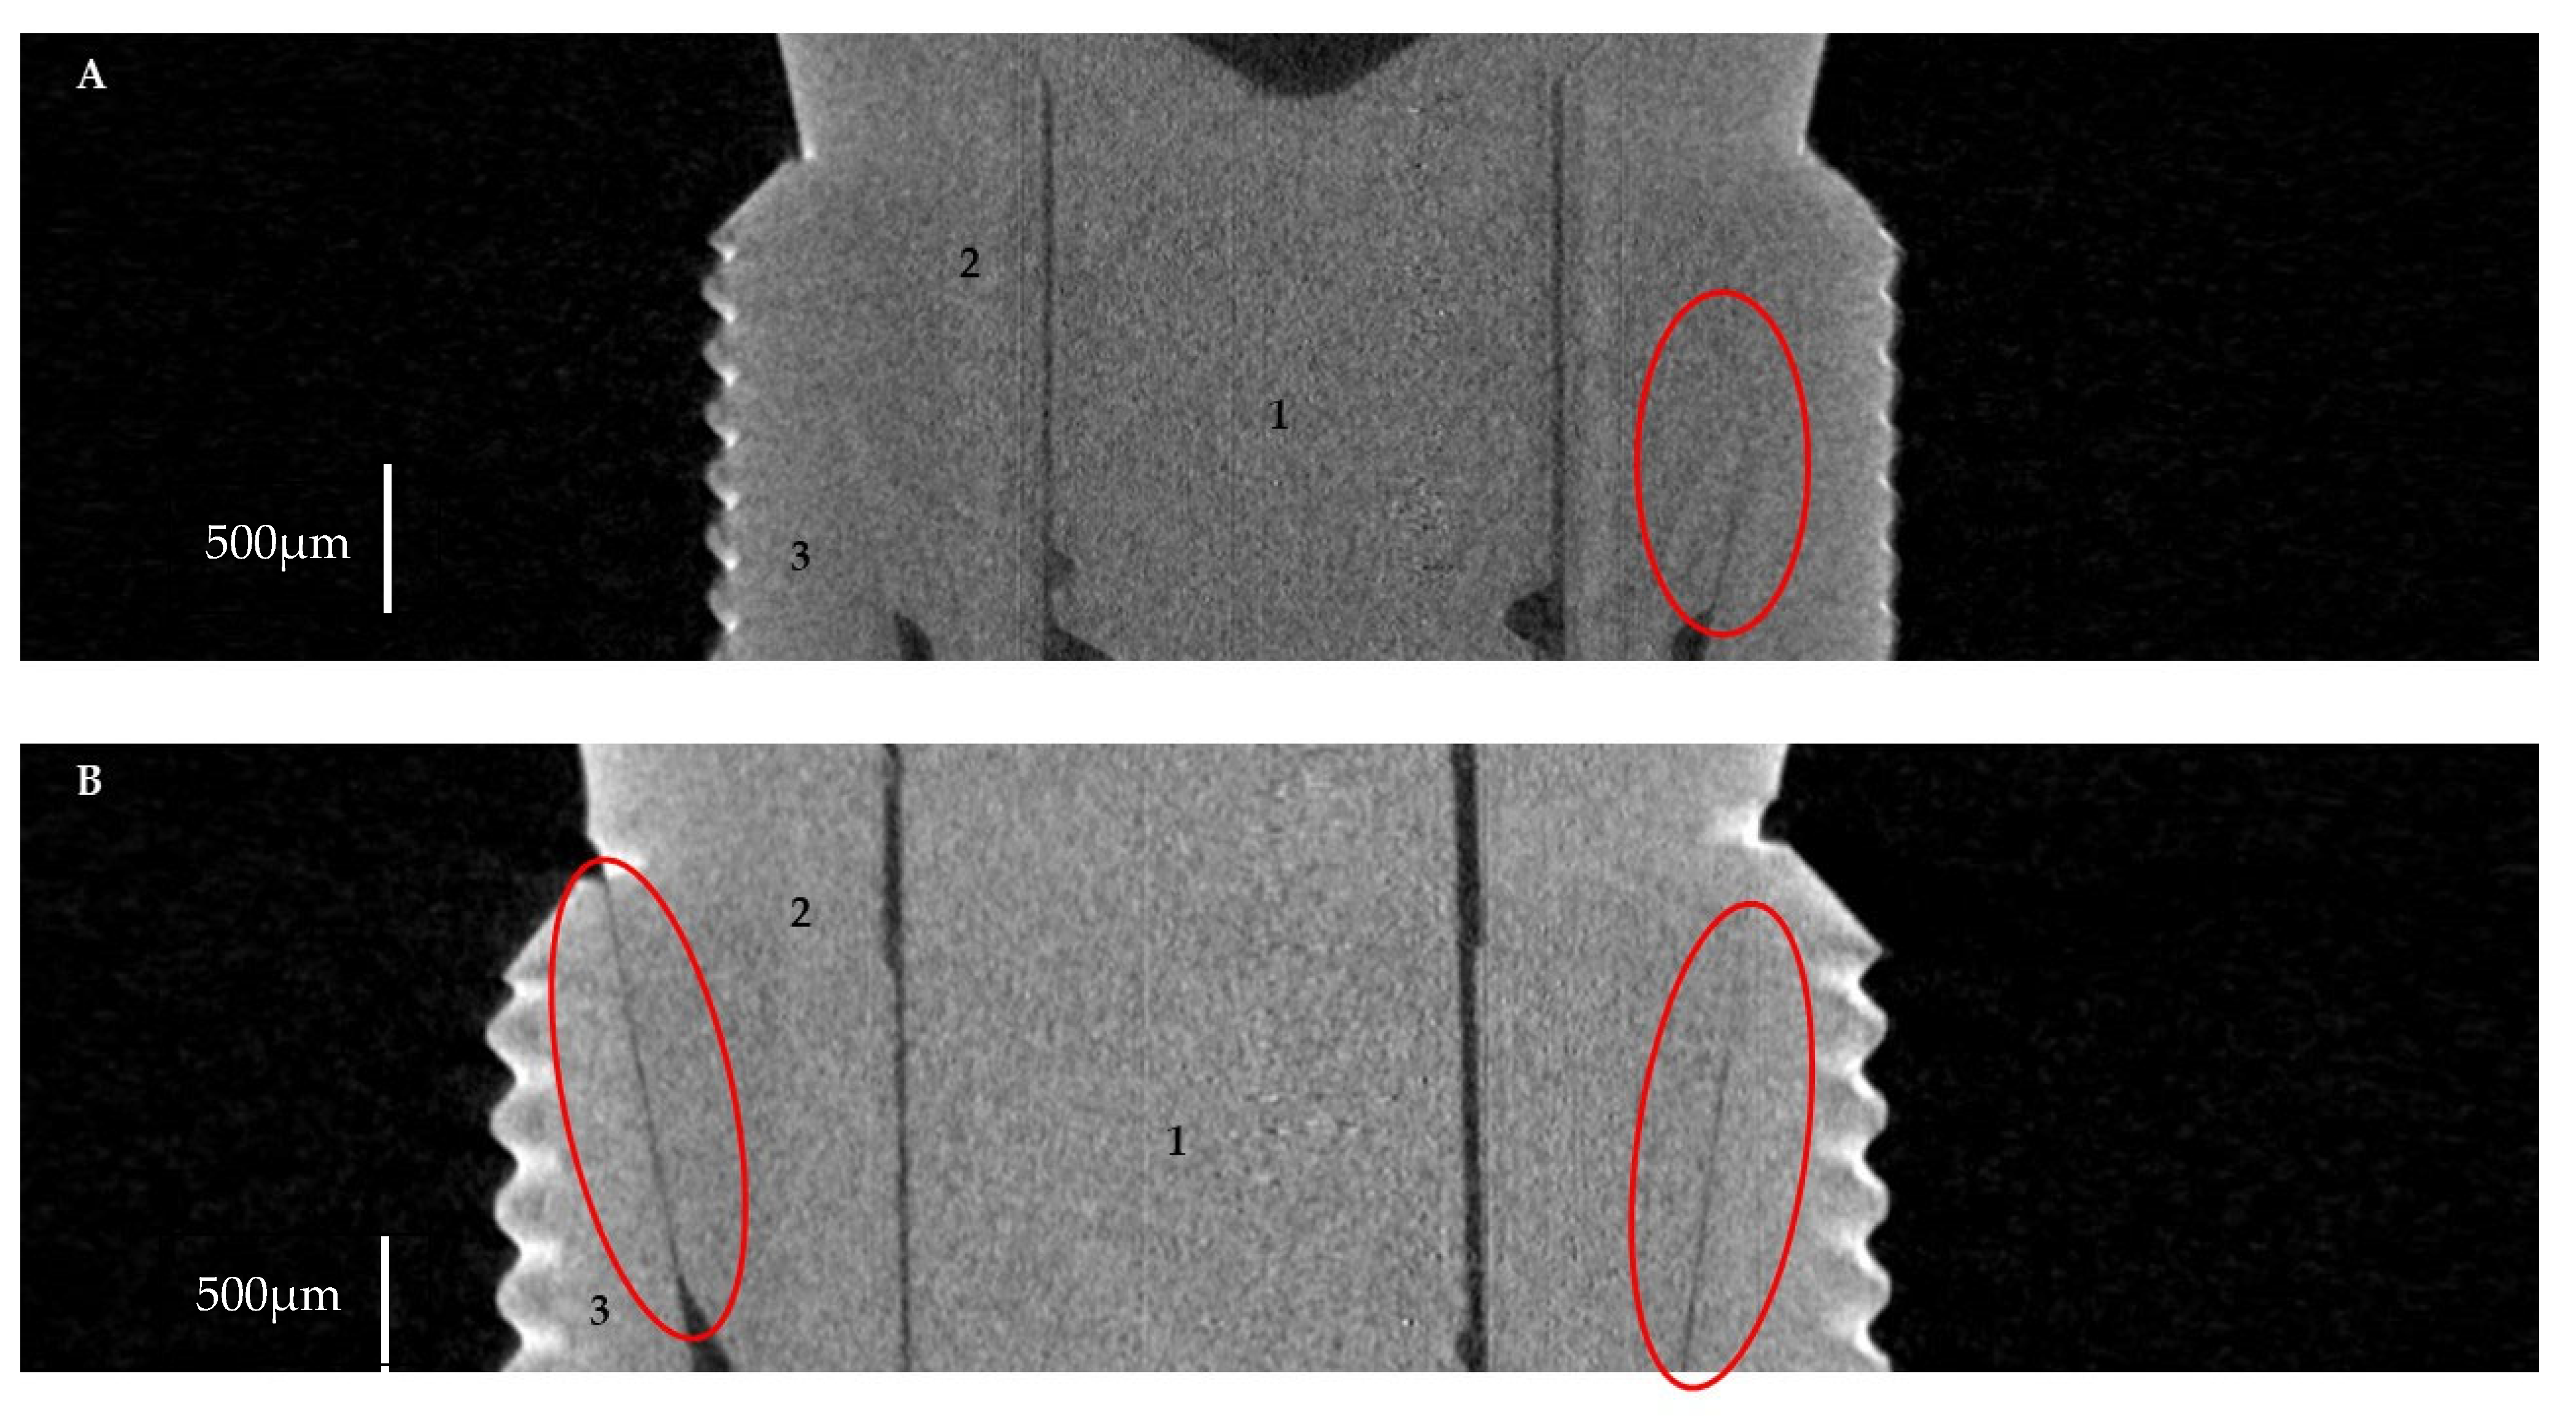

2.2.1. Horizontal Microgap (Linear Measurement)

3.1. Horizontal Microgap (Linear Measurement)